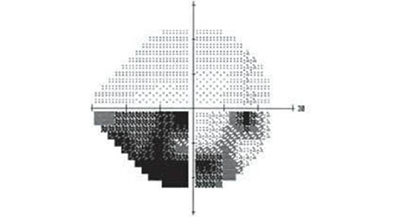

视野指的则是眼睛看向正前方时所能看到的空间范围。在检查中,视野常被划分为四个象限,下图就是一位青光眼患者的视野检查结果,图中黑色部分为视野缺损的部分。